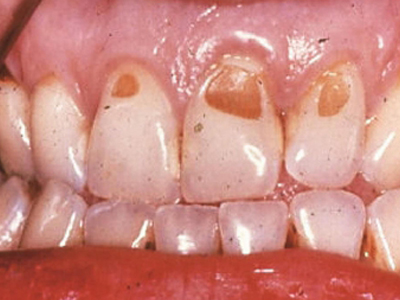

酸蚀症牙齿缺损不平整图

酸蚀症患者的牙齿会发生缺损,轻度时仅表现为牙齿尖端凹凸不平,有少量骨质缺失,缺损处有黄褐色至红褐色斑点,该病可能是长期接触外源性酸性物质而致病。